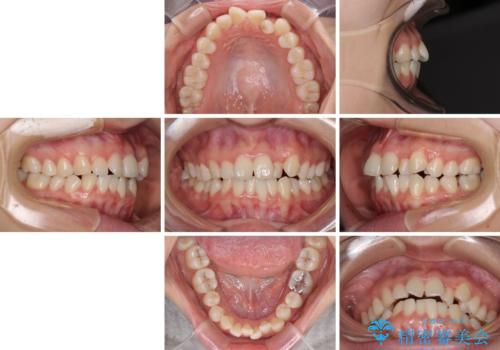

- 前歯のデコボコを気にして来院された患者様です。

前歯のデコボコはもちろん気になるところですが、舌の突出癖により上下の前歯に大きな隙間がある状態でした。

上下前歯が非接触である開咬は、インビザラインによる治療がお勧めではありますが、非抜歯矯正か抜歯矯正か悩む口元であり、途中抜歯矯正に切り替えたときに対応しやすいよう、ワイヤー装置にて治療を行うこととしました。